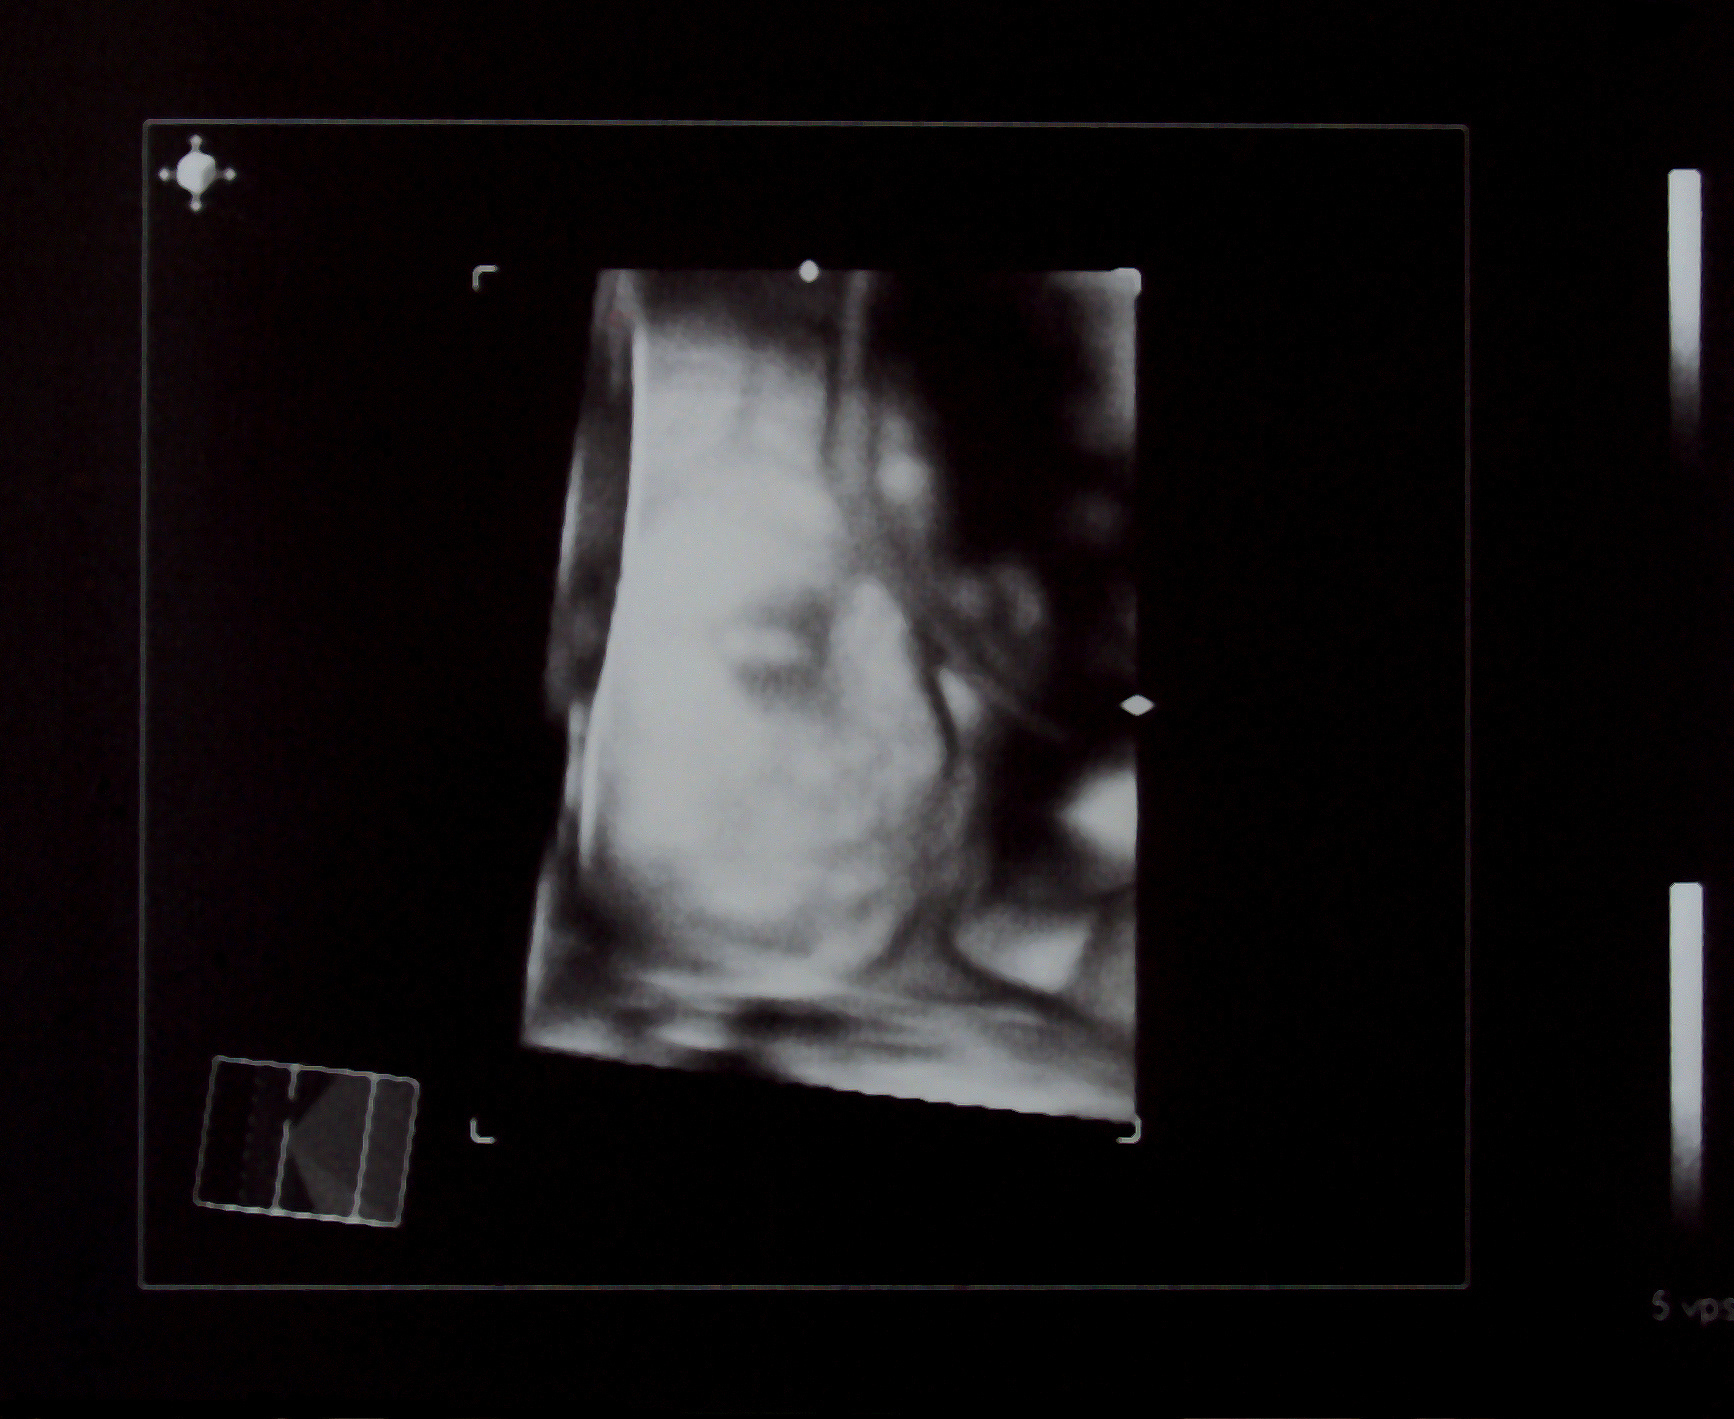

四维羊水最大深度80.7mm表示胎儿周围羊水的最大深度为80.7毫米。羊水是胎儿在子宫内生长发育过程中所处的环境,它提供了对胎儿的保护和支持。四维超声检查是一种通过多个角度观察胎儿的实时三维图像的技术,可以提供更详细和准确的胎儿生长和发育信息。80.7mm的羊水深度在正常范围内,这意味着胎儿的羊水环境良好。